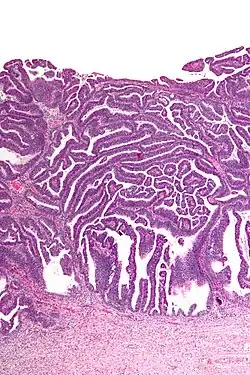

| Micrograph of a villoglandular adenocarcinoma the cervix. H&E stain. | |

The name of the lesion describes it microscopic appearance. It has nipple-like structures with fibrovascular cores (papillae) that are long in relation to their width (villus-like), which are covered with a glandular pseudostratified columnar epithelium.

Very low magnification -

Intermediate magnification -

Very high magnification